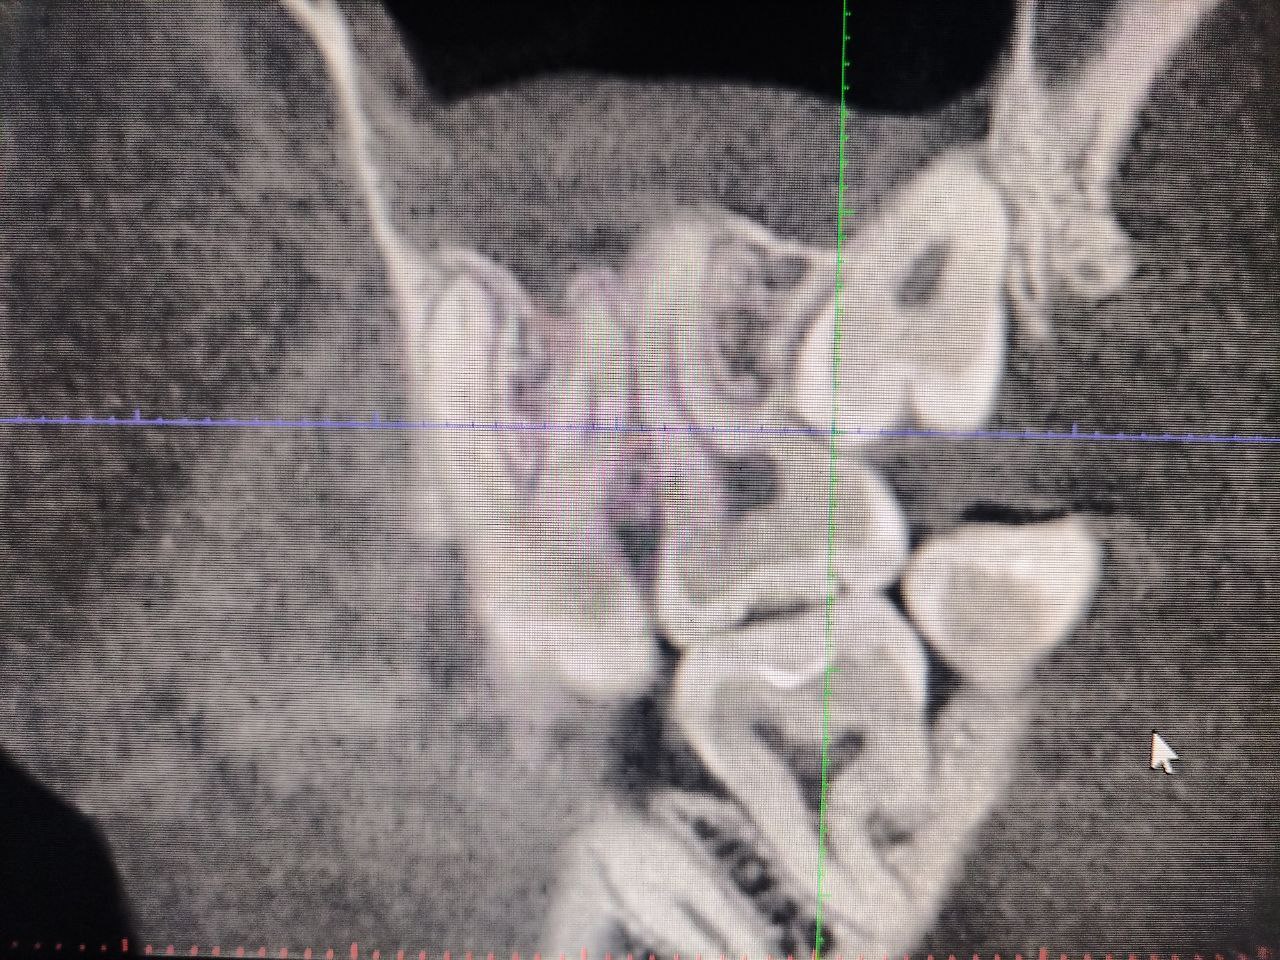

Конусно-лучевая компьютерная томография

Для быстрой и точной диагностики заболеваний челюстно-лицевой области в нашей клинике используется прогрессивный метод рентгенодиагностики – конусно-лучевая компьютерная томография, или как ее еще называют компьютерная 3D диагностика. Это новейший и самый безопасный способ проведения не только рентгена зубов, но и